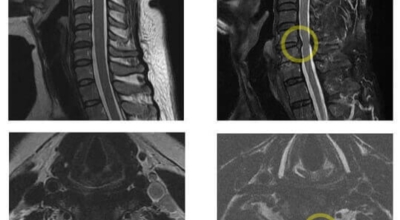

목디스크 증상이 나타날때 빨리 발견하여 비수술 치료를 받고 꾸준히 관리하는 것이 베스트이죠. 목디스크 환자 중 수술을 진행하는 환자는 2% 미만으로 현저히 적다고 해요. 수술을 진행하는 경우는 감각이 느껴지지 않는 마미증후군이나, 한쪽 다리가 눈에 띌 정도로 야윈 경우에만 진행하므로 올바른 자세 교정만으로도 충분히 호전될 수 있는 질병이죠. 목에 연관된 검사는 MRI나 CT를 이용해요. 그러나 전자의 경우 비용이 굉장히 비싸기 때문에 디스크 증세가 확실하다고 생각될 경우에만 선택적으로 하고 의무적으로 하는 건 아니니까 비용에 대해선 부담을 가지지 마시길 바래요.